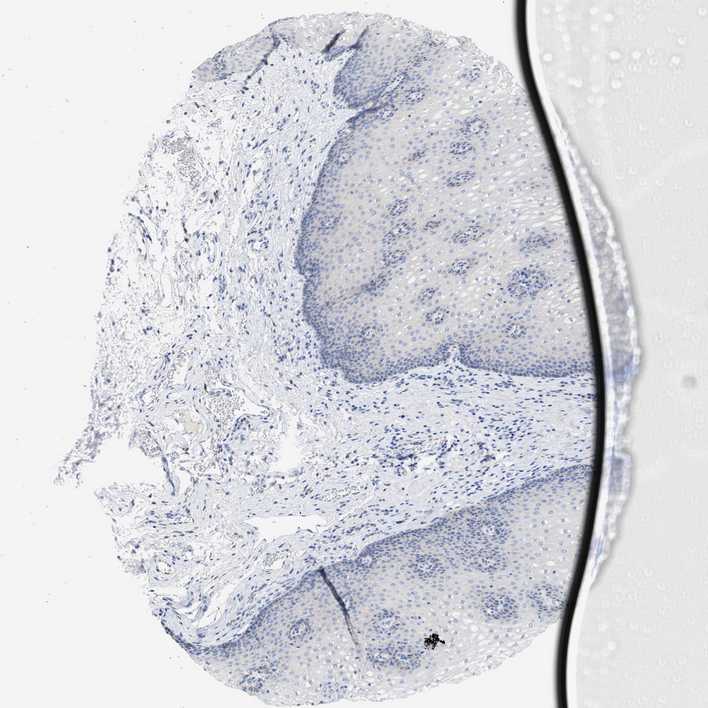

ESOPHAGUS - Antibody stainingi

Antibody staining in the annotated cell types in the current human tissue is reported as not detected, low, medium, or high, based on conventional immunohistochemistry profiling in selected tissues. This score is based on the combination of the staining intensity and fraction of stained cells.

Each image is clickable and will lead to virtual microscopy that enables deeper exploration of all samples and also displays staining intensity scores, fraction scores and subcellular localization as well as patient and tissue information for each sample.

Antibody HPA016816Antibody HPA017382

Squamous epithelial cells Not detectedNot detected